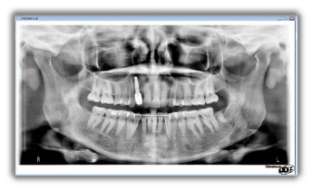

Gendex Orthoralix 8500 DDE vanta un design moderno che combina un’estrema funzionalità e semplicità d’uso con una gradevole estetica high-tech veramente accattivante, che non mancherà di valorizzare il vostro studio. Le immagini sono acquisite in modalità digitale mediante sensore CCD che la più recente ed avanzata tecnologia mette a disposizione. Il sistema dispone di quattro proiezioni: panoramica adulto, panoramica bambino, ATM frontale e ATM laterale.

Posizionato correttamente il paziente, Orthoralix 8500 DDE per mezzo della movimentazione multi-motorizzata dell’assieme monoblocco/sensore è in grado di generare sofisticate proiezioni specifiche per l’obiettivo diagnostico, producendo così immagini fedeli e nitide dell’intera regione dento-maxillo-facciale. L’ingrandimento si mantiene costante durante tutta l’esposizione garantendo immagini panoramiche caratterizzate da una minima distorsione radiografica.

Le immagini del nuovo Orthoralix 8500 DDE sono nitide e definite anche grazie alla piccola macchia focale del tubo radiogeno (solo 0,4 mm la più piccola nel settore). Utilizzando i più recenti algoritmi di elaborazione delle immagini digitali applicati ai dati che compongono la panoramica di questo sistema di nuova generazione, si ottengono radiografie che riproducono con precisione aree anatomiche critiche dei pazienti.